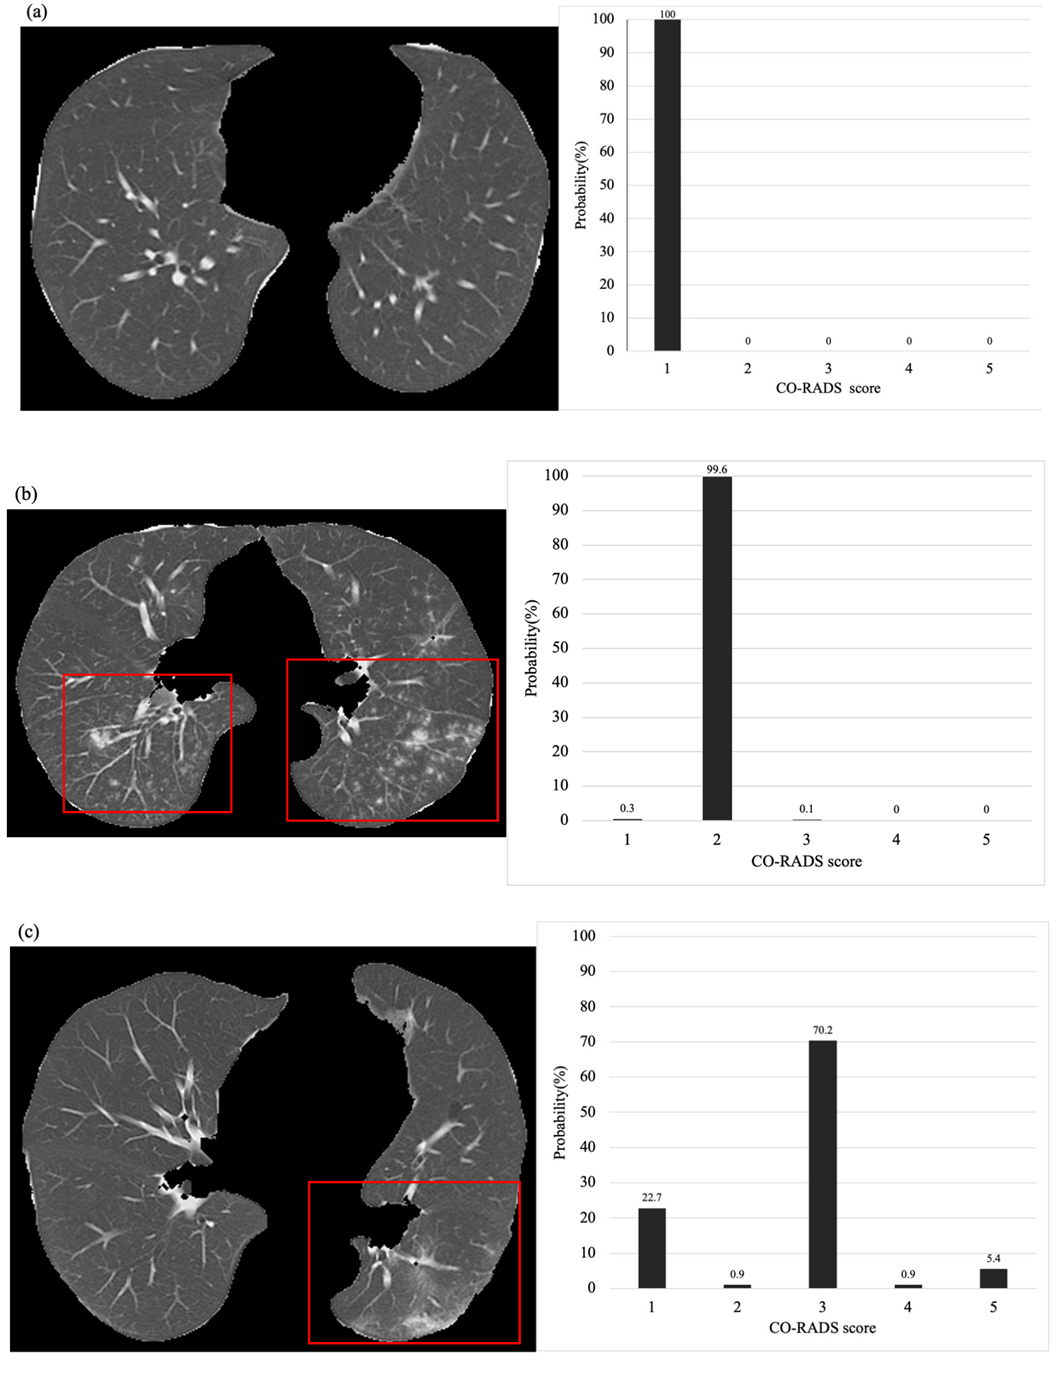

Table 2 summarizes the patient characteristics for the training and test datasets. Figure 4 shows the CT images of three representative cases and the probability of obtaining different CO-RADS scores based on the deep-learning classification model. There were no significant differences in the distribution of age between the training and test data (p = 0.06), male-to-female ratio among patients (p = 0.07), and CO-RADS score distribution (p = 0.12).

Figure 4.

Representative output from the classification model. (a) The CT image shows no abnormal density in both lungs. The classification model presented a 100% probability of a CO-RADS score of 1. (b) CT imaging shows multiple centrilobular nodules in both lungs. The classification model presented an approximately 99% probability of obtaining a CO-RADS score of 2. (c) The CT images show unilateral nonspecific ground-glass opacity in the dorsal aspect of the left lung. The classification model presented an approximately 70% probability of obtaining a CO-RADS score of 3. Although a score of 3 was determined, the possibility of 1 or 5 was also suggested. (d) CT imaging shows bilateral subpleural predominant ground-glass opacity and consolidation and strong emphysematous changes in the background. In classification models, a CO-RADS score of 4 is most likely. (e) The CT image shows crazy-paving-like ground-glass opacity in the bilateral subpleural areas. The classification model also presents the highest possibility of a CO-RADS score of 5.